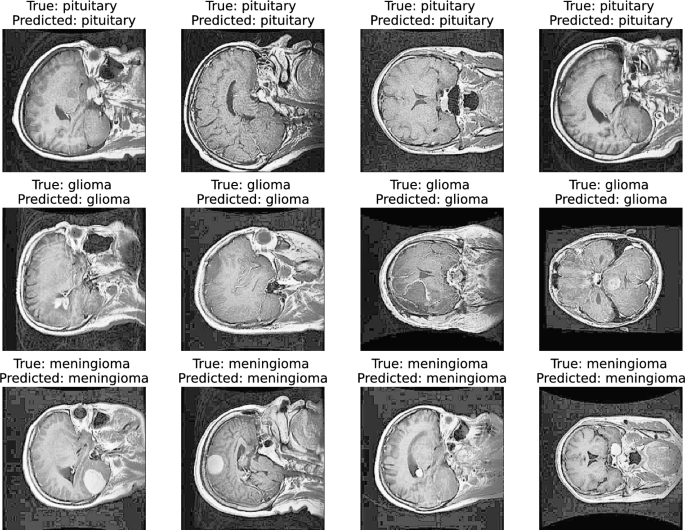

Performance test measurement Fig. 8 presents an analysis of test performance showcasing our efficient ensemble (SDG+GSWO) model in brain tumor classification tasks. By visualizing the performance for several sample images, we demonstrate the model’s effectiveness, achieving perfect predictions for all samples.

The classification report analysis (Table 4) compares the performance of various deep learning models for brain tumor classification under two data configurations: No-SDG and SDG. The table includes precision, recall, and F1-score for the three tumor classes: pituitary, meningioma, and glioma. Under No-SDG, models such as GSWO and GAWO consistently achieve high scores across all classes. GSWO demonstrates exceptional performance with a precision, recall, and F1-score of 99.80 for pituitary and glioma, and 99.60 for meningioma. Other models, like Xception and ResNet50V2, also perform well but show slightly lower values in recall and F1-score, particularly for meningioma. This indicates that while these models are strong, GSWO is the most reliable across all tumor types in the No-SDG configuration. When SDG is applied, there is a noticeable improvement in performance for most models, particularly GSWO, which further enhances its precision, recall, and F1-score to 99.93, 99.80, and 99.87 for pituitary, meningioma, and glioma, respectively. GAWO also improves, with scores reaching 99.87, 99.76, and 99.80, demonstrating its robustness with SDG. Xception, ResNet50V2, and ResNet152V2 show consistent improvements in all metrics, but still lag behind GSWO and GAWO, especially in recall and F1-score for meningioma. Overall, the GSWO with SDG model emerges as the best-performing model across all tumor types, offering superior precision, recall, and accuracy scores, demonstrating the effectiveness of synthetic data generation in improving model performance for brain tumor classification.